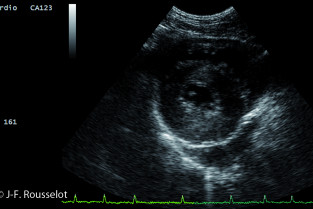

L’examen échocardiographique

L’examen échodoppler normal

Echodoppler de la maladie valvulaire mitrale

Echodoppler des cardiomyopathies canines et félines

Echodoppler des cardiopathies congénitales

Echographie thoracique non cardiaque

Présentation de films et de cas cliniques